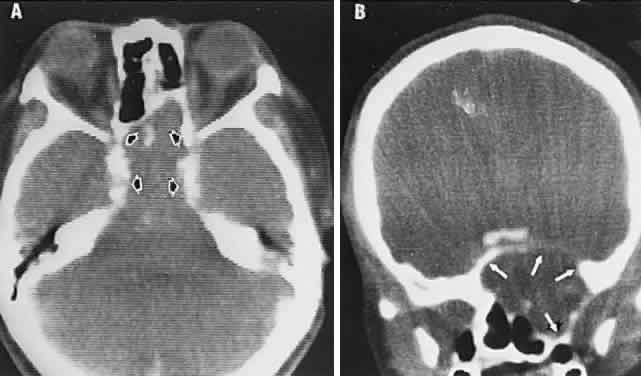

With acute infarction, the retina becomes opaque and takes on a creamy or gray appearance. Atheromatous material in the form of “bright plaques” of cholesterol or other microemboli may be seen, especially lodged at arterial bifurcations (Fig. 5). Segmental arteriolar mural opacification (see Fig. 5D) may follow retinal microembolization by weeks to months, and such sheathing may be as useful as the recognition of the cholesterol embolus itself.43 ERG may show diminished B-wave amplitude, a finding indicating inner retinal ischemia. Weeks following retinal infarction, the optic disc becomes pale, and the arterial tree becomes narrowed in the sector corresponding to the arterial occlusion.

Fig. 5. Retinal microembolic phenomena. A. Bright cholesterol plaque (arrow) impacted at an arterial bifurcation. Thin crystal does not obstruct flow. B. Cholesterol crystals in disc vessels (arrows). Often, the plaque appears larger than the vessel diameter. C. Infarcted opaque retina. The artery contains emboli (? fibrin platelets) that have obstructed flow. D. Reactive opacification of the arterial wall. Fluorescein angiography demonstrated flow through this formerly occluded vessel.